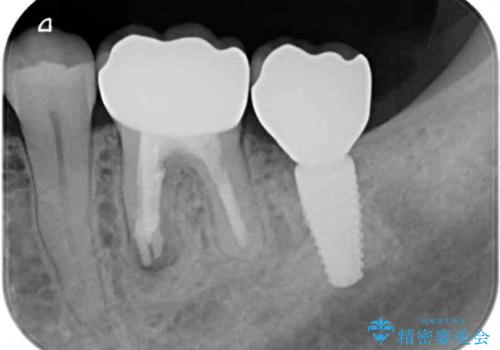

インプラントにはストローマン社のSLActiveを使用し、埋入から補綴までおよそ3か月と、短期間で治療を進めることができました。